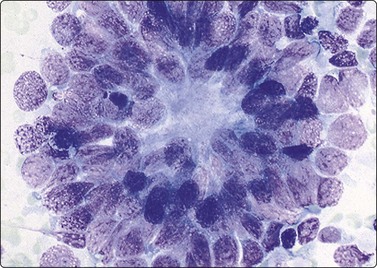

Neuroblastoma usually forms a well-defined solid tumor <10 cm in size with hemorrhage and extentive necrosis. The FNA usually yields hypercellular smears with predominant individually scattered small anaplastic cells, showing prominent nuclear molding.27,41,42 The prototypical neuroblastic cells have high nuclear to cytoplasmic ratios with single nuclei that are oval to slightly irregular in shape containing evenly dispersed granular chromatin (salt and pepper) and small to inconspicuous nucleoli (Fig. 17.1). Small round cells are arranged in moderately or well-formed Homer-Wright rosettes surrounding centrally located neuropil, which stains pink or blue–gray in Giemsa-stained smears. The presence of Homer-Wright rosettes is diagnostic but not present in all cases (Fig. 17.2). Neuropil, either associated with the rosettes or present in the smear background, is the most helpful cytologic feature for rendering a definitive cytologic diagnosis of neuroblastoma.34 Neuropil consists of a fibrillary tangle of neuritic processes with or without associated neuroblastic cells (Fig. 17.3). Mitotic–karyorrhectic cells and calcifications can occasionally be recognized in aspirate smears. Larger differentiating neuroblasts with moderate amounts of cytoplasm and binucleated to multinucleated ganglion cells can also be present in the smear. Some neuroblastomas may undergo different grades of maturation, forming ganglioneuroblastoma or ganglioneuroma. In ganglioneuroblastoma, the smear is pleomorphic with prominent anisonucleosis and abundant neuropil background but without ganglion cells, while ganglioneuroma demonstrates characteristic ganglion cells (Fig. 17.4).27,42

image

Fig. 17.4 Neuroblastoma

Compared with neuroblastic cells, neoplastic ganglion cells (arrows) demonstrate larger nuclei with prominent nucleoli, and moderate amounts of coarsely granular cytoplasm. These cells are seen in the two related lesions, ganglioneuroblastoma and ganglioneuroma (Diff-Quik, ×400).